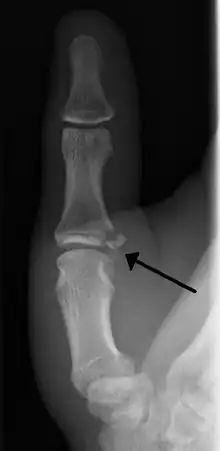

| Avulsion fractures of the ulnar base of the proximal phalanx of the thumb ( Gamekeeper's fracture ) | |

- Avulsion of distal UCL causing the pulling off of a bone chip off the proximal phalanx base.[4]

When approaching this type of injury, the physician must first determine whether there is an incomplete rupture (or sprain) of the UCL, or a complete rupture. If the UCL is completely disrupted, the physician must then determine whether there is interposition of the adductor aponeurosis (Stener lesion), or simply a complete rupture of the UCL with anatomic or near-anatomic position. Radiographs are helpful in determining the possible presence of an avulsion fracture of the proximal phalanx insertion site of the ulnar collateral ligament. Stress examination, or one done under fluoroscopic guidance, can help determine the integrity of the ligament.